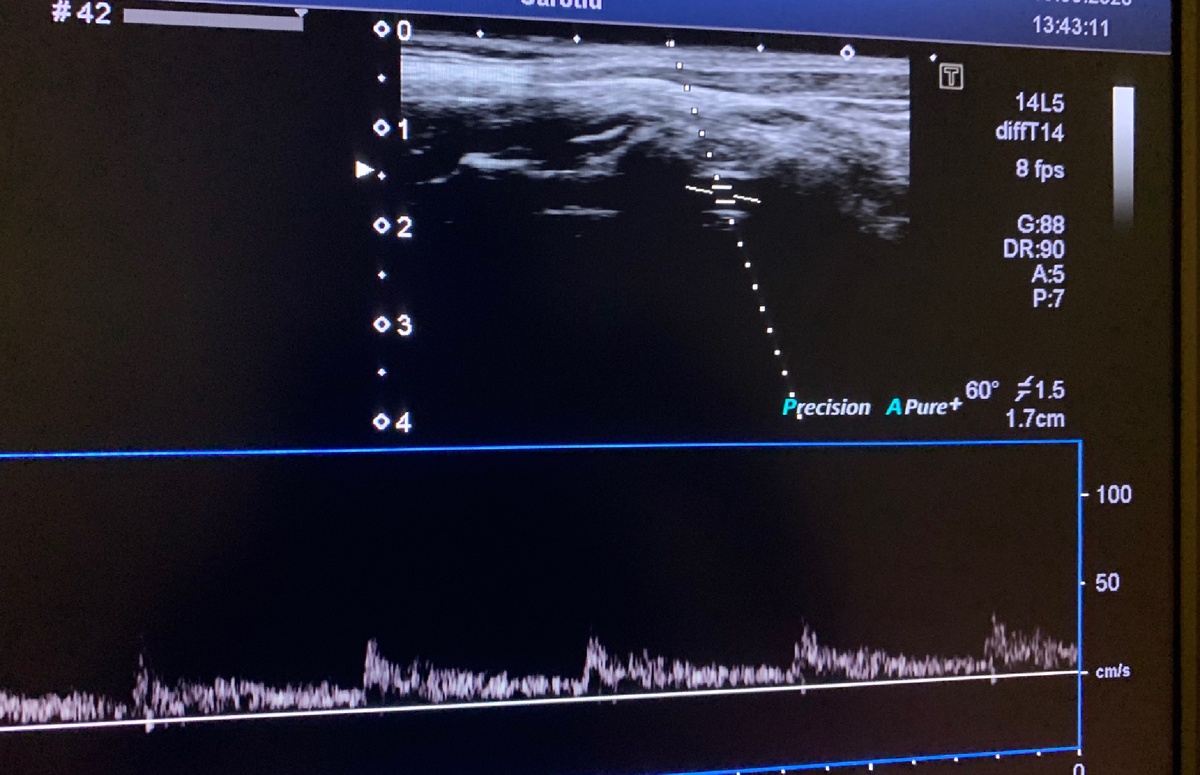

Одним из часто назначаемых неврологом исследований является ультразвуковая доплерография/УЗИ сосудов шеи. Синонимом является УЗДГ брахиоцефальных артерий.

Вертебро-базилярная недостаточность возникает из-за недостаточного кровоснабжения мозга, а самым частым симптомом является головокружение. На УЗДГ при этом отмечается снижение скорости кровотока в позвоночных и/или основной артериях.

Нормальные показатели кровотока в позвоночной артерии

Компрессия дисков шейных позвонков, костные разрастания, а также спазм мышц шеи могут приводить к сдавлению одной или двух позвоночных артерий, что проявляется позвоночными (вертеброгенными) влияниями. На УЗДГ это может проявляться ассиметрией диаметра и скорости кровотока, повышением сосудистого тонуса, снижением скоростных показателей.